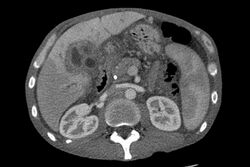

Abdominal imaging

CT scan showing cholangiocarcinoma

Ultrasound of the liver and biliary tree is often used as the initial imaging modality in people with suspected obstructive jaundice.[49][50] Ultrasound can identify obstruction and ductal dilatation and, in some cases, may be sufficient to diagnose cholangiocarcinoma.[51] Computed tomography (CT) scanning may also play an important role in the diagnosis of cholangiocarcinoma.[52][53][54]